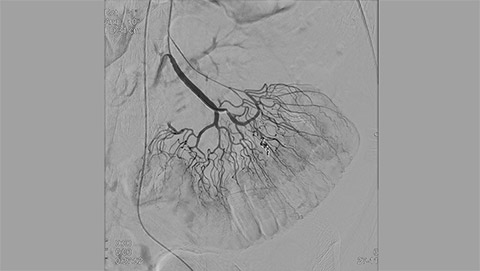

Live 3D MR/CT Roadmap fuses live 2D fluoroscopy on a pre-acquired MR or CT image, which may reveal hidden anomalies and enable real-time motion compensated navigation to support interventional procedures. Live 3D MR/CT Roadmap provides full 3D view for guidance of guidewires, catheters and coils through complex vessel and anatomical structures.

High-resolution 3D-RA vascular images or previously acquired 3D segmented MRA or CTA data is registered to the current patient position through a low X-ray dose 3D-RA scan, allowing ‘re-use’ of contrast and X-ray doses.